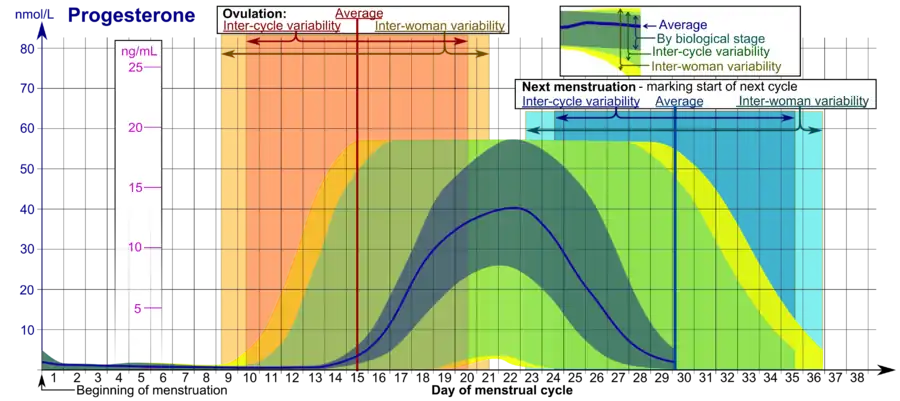

In women, progesterone levels are relatively low during the preovulatory phase of the menstrual cycle, rise after ovulation, and are elevated during the luteal phase, as shown in the diagram above. Progesterone levels tend to be less than 2 ng/mL prior to ovulation and greater than 5 ng/mL after ovulation. If pregnancy occurs, human chorionic gonadotropin is released, maintaining the corpus luteum and allowing it to maintain levels of progesterone. Between 7 and 9 weeks, the placenta begins to produce progesterone in place of the corpus luteum in a process called the luteal-placental shift.[131]

Blood test results should always be interpreted using the reference ranges provided by the laboratory that performed the results. Example reference ranges are listed below.

| Person type | Reference range for blood test | ||

|---|---|---|---|

| Lower limit | Upper limit | Unit | |

| Female - menstrual cycle | (see diagram below) | ||

| Female - postmenopausal | <0.2[141] | 1[141] | ng/mL |

| <0.6[142] | 3[142] | nmol/L | |

| Female on oral contraceptives | 0.34[141] | 0.92[141] | ng/mL |

| 1.1[142] | 2.9[142] | nmol/L | |

| Males ≥16 years | 0.27[141] | 0.9[141] | ng/mL |

| 0.86[142] | 2.9[142] | nmol/L | |

| Female or male 1–9 years | 0.1[141] | 4.1[141] or 4.5[141] | ng/mL |

| 0.3[142] | 13[142] | nmol/L | |

• The ranges denoted By biological stage may be used in closely monitored menstrual cycles in regard to other markers of its biological progression, with the time scale being compressed or stretched to how much faster or slower, respectively, the cycle progresses compared to an average cycle.

• The ranges denoted Inter-cycle variability are more appropriate to use in non-monitored cycles with only the beginning of menstruation known, but where the woman accurately knows her average cycle lengths and time of ovulation, and that they are somewhat averagely regular, with the time scale being compressed or stretched to how much a woman's average cycle length is shorter or longer, respectively, than the average of the population.

• The ranges denoted Inter-woman variability are more appropriate to use when the average cycle lengths and time of ovulation are unknown, but only the beginning of menstruation is given.

Sources